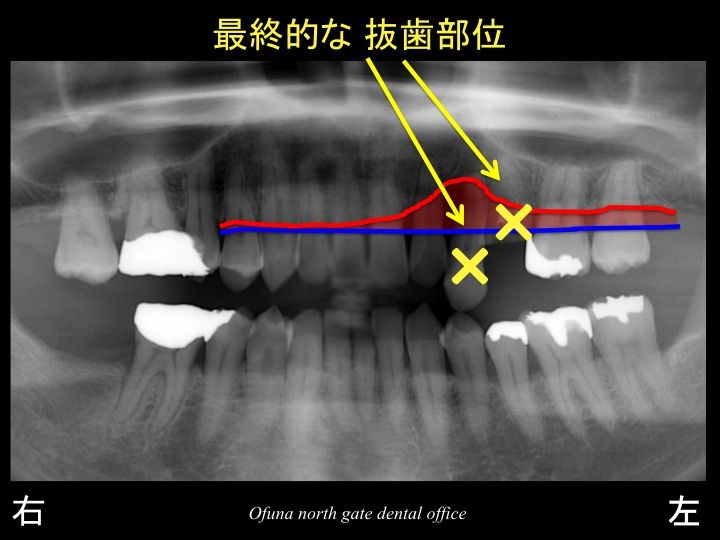

いつものように 骨吸収の状態を分かりやすくするために

骨吸収の状態を線で書いたのが以下のレントゲンになります。

青線が骨吸収を起こす前の骨の位置です。

赤線は、現在の骨の位置です。

かなりの骨吸収が起こっているのが分かるかと思います。

さらに わかりやすくするために、

骨吸収部位を赤色で表示します。

今回グラグラしている歯が いかに骨吸収が大きいかが分かると思います。

等を考慮して 以下の2歯は保存が難しいと判断しました。

まず、上顎左側の犬歯です。

ここで問題となったのが、以下の歯です。

この歯は保存が可能なのでしょうか?

この歯の骨は、60%以上も骨吸収が進行しています。

今回一番問題となったのが、

2歯を抜歯するか?

3歯を抜歯するかです。

最終的な治療計画は、2歯を抜歯し、手前の歯は徹底した歯周病治療 と噛み合わせの治療を行い、保存することになりました。